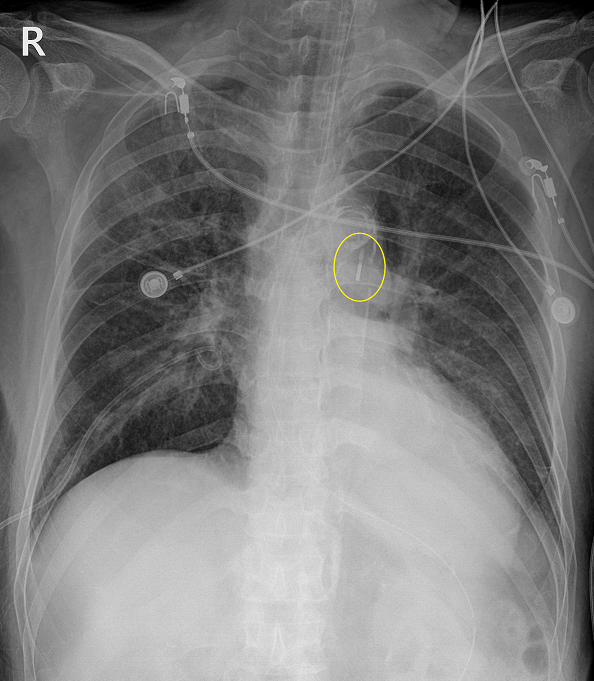

실제 환자는 지속적으로 혈압이 저하되는 상황에서 심장수술을 받기엔 상태가 너무 좋지 않아 IABP를 삽입하기에 이르렀다.

이렇게 환자의 가족들이 연락이 안 되면서 서로의 책임을 전가한 지 3일째, 그사이 환자는 한 번의 심정지가 발생하였고, IABP를 넣은 쪽 다리는 허혈증상으로 인해 괴사의 조짐이 시작되고 있었다.

그 이후엔 환자의 연명치료 중단을 위한 법적 동의서(POLST)를 받고, 환자의 연명치료에 해당하는 승압제의 사용, 기관삽관, IABP를 중단하였다.